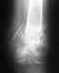

Проведена Ахиллопластика лавсановой лентой.

Проведена Ахиллопластика лавсаовой лентой 6 июля 2007г. В течение 2-х месяцев воссатовление шло успешно. После в районе пятки шов разошолся и не срастается до сегоднешнего дня. Диагоноз отторжение лавсановой нити. Врач планирует удалить её. Было ли в Вашей практике подобное, Ваши действия? С уважением, Алексей.